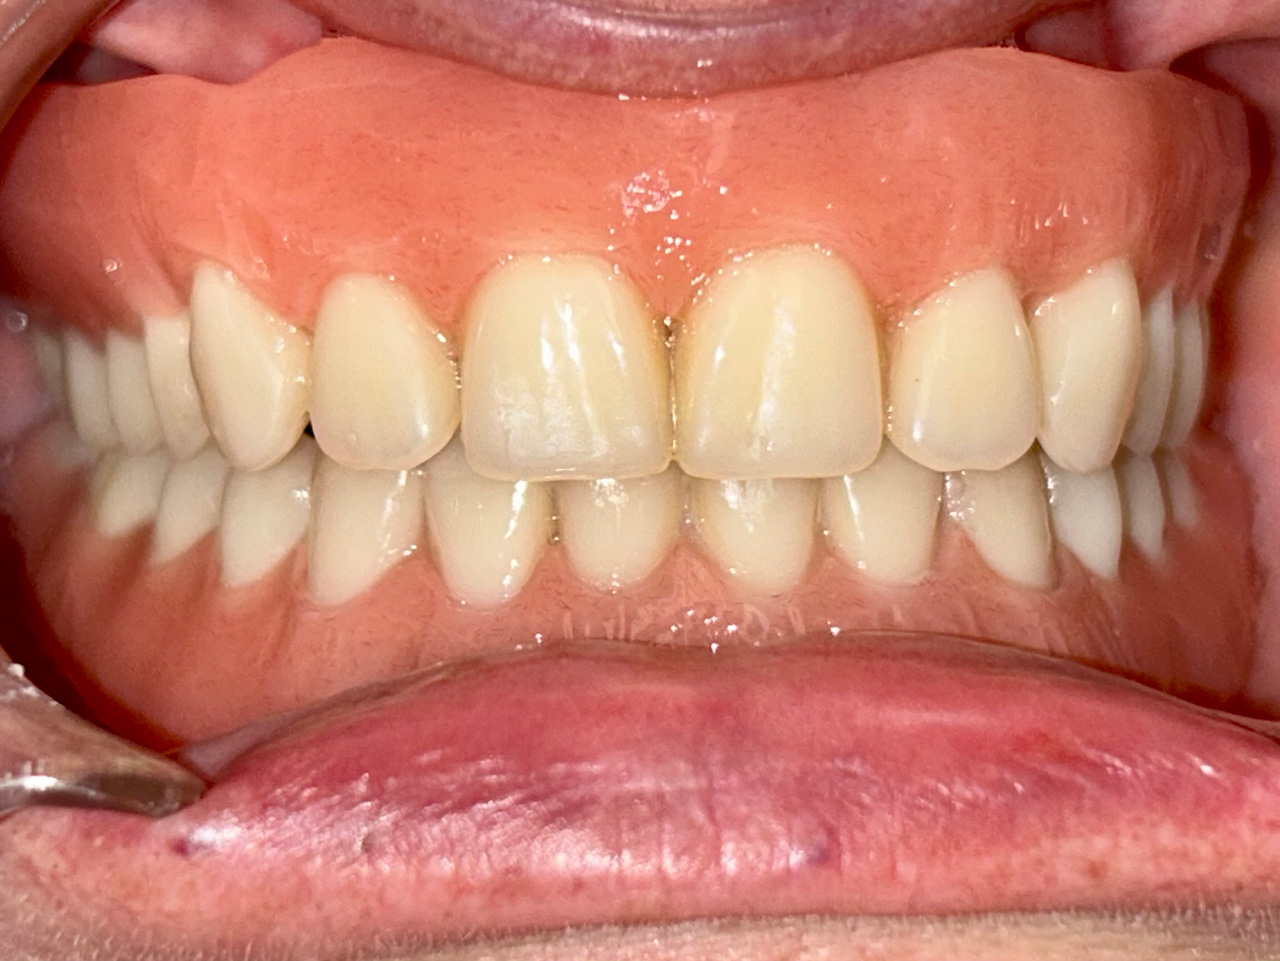

Teljes fogatlanság helyreállítása 2 nap alatt

Teljes fogatlanság helyreállítása 2 nap alatt azonnal terhelhető svájci IHDE implantátumokkal és PMMA műanyag hidakkal. Intraorális szkennerrel vettünk lenyomatot az implantáció után, és erre a digitális mintára készítette el a fogtechnika a hidak digitális tervezését, majd faragta ki műanyagból. Ezt a gyors munkát az azonnal terhelhető implantátumok és a digitális lenyomat, tervezés segítségével tudtuk megcsinálni mindössze 2 nap alatt. Dr. Kelemen Péter és a Symbion Fogtechnika munkája.